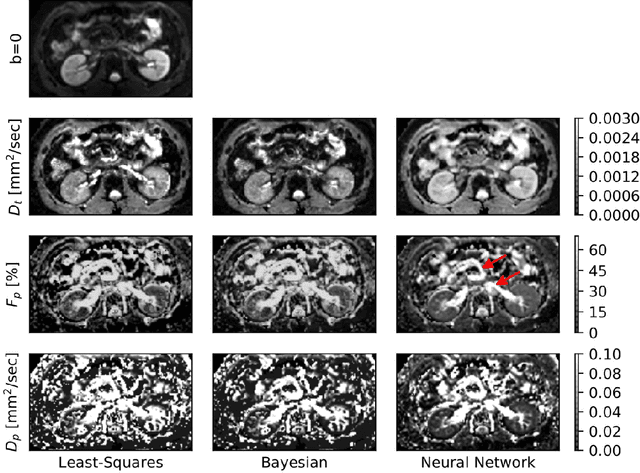

Abstract:Purpose: This prospective clinical study assesses the feasibility of training a deep neural network (DNN) for intravoxel incoherent motion (IVIM) model fitting to diffusion-weighted magnetic resonance imaging (DW-MRI) data and evaluates its performance. Methods: Approval for this study was obtained by the responsible ethics committees and written informed consent was obtained from all accrued subjects. In May 2011, ten male volunteers (age range: 29 to 53 years, mean: 37 years) underwent DW-MRI of the upper abdomen on 1.5T and 3.0T magnetic resonance scanners. Regions of interest in the left and right liver lobe, pancreas, spleen, renal cortex, and renal medulla were delineated independently by two readers. DNNs were trained for IVIM model fitting using these data; results were compared to least-squares and Bayesian approaches to IVIM fitting. Intraclass Correlation Coefficients (ICC) were used to assess consistency of measurements between readers. Intersubject variability was evaluated using Coefficients of Variation (CV). The fitting error was calculated based on simulated data and the average fitting time of each method was recorded. Results: DNNs were trained successfully for IVIM parameter estimation. This approach was associated with high consistency between the two readers (ICCs between 50 and 97%), low intersubject variability of estimated parameter values (CVs between 9.2 and 28.4), and the lowest error when compared with least-squares and Bayesian approaches. Further, fitting by DNNs was several orders of magnitude quicker than the other methods. Conclusion: DNNs are recommended for accurate and robust IVIM model fitting to DW-MRI data. Suitable software is available at (1).